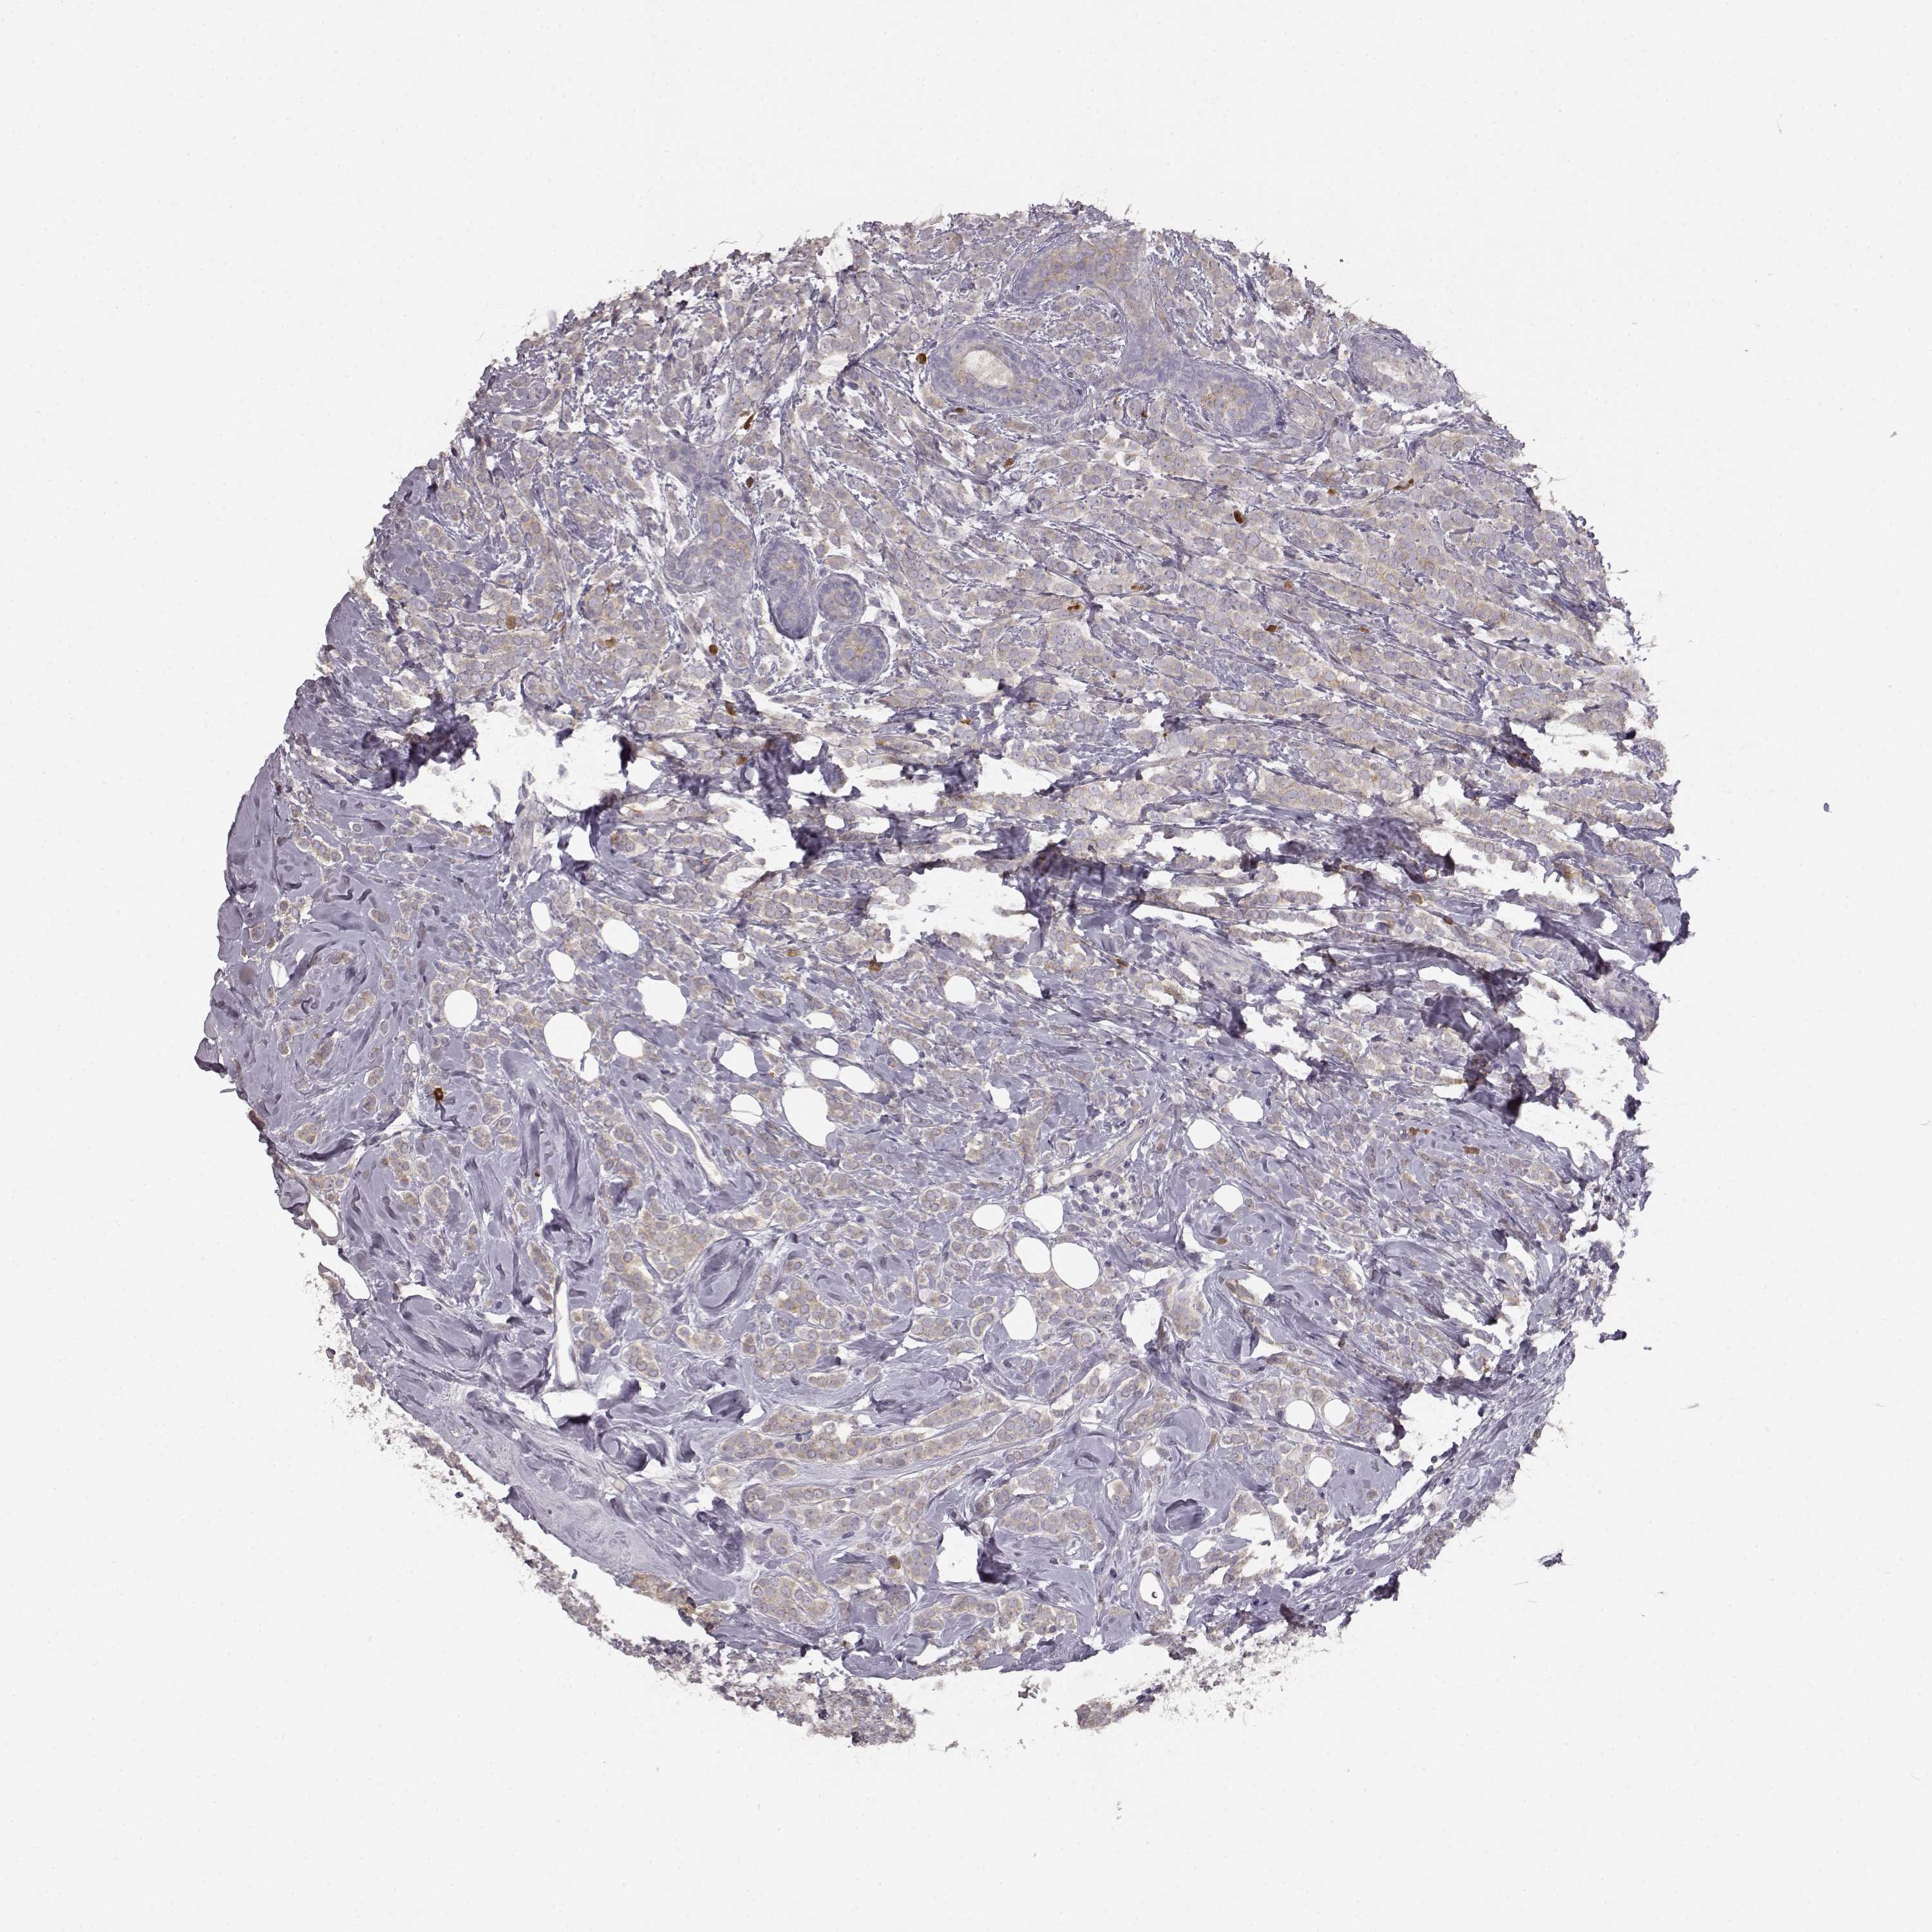

CANCER BREAST CANCER Show tissue menu

BRCA TCGA BRCA VALIDATION PROTEIN EXPRESSION